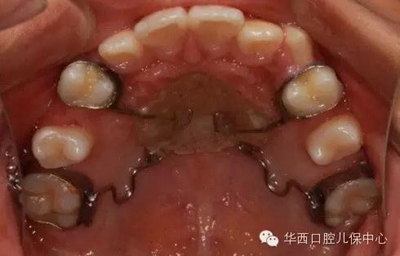

圖為下頜乳磨牙早失,未行間隙管理,繼承恒牙無法萌出(黃圈內(nèi))